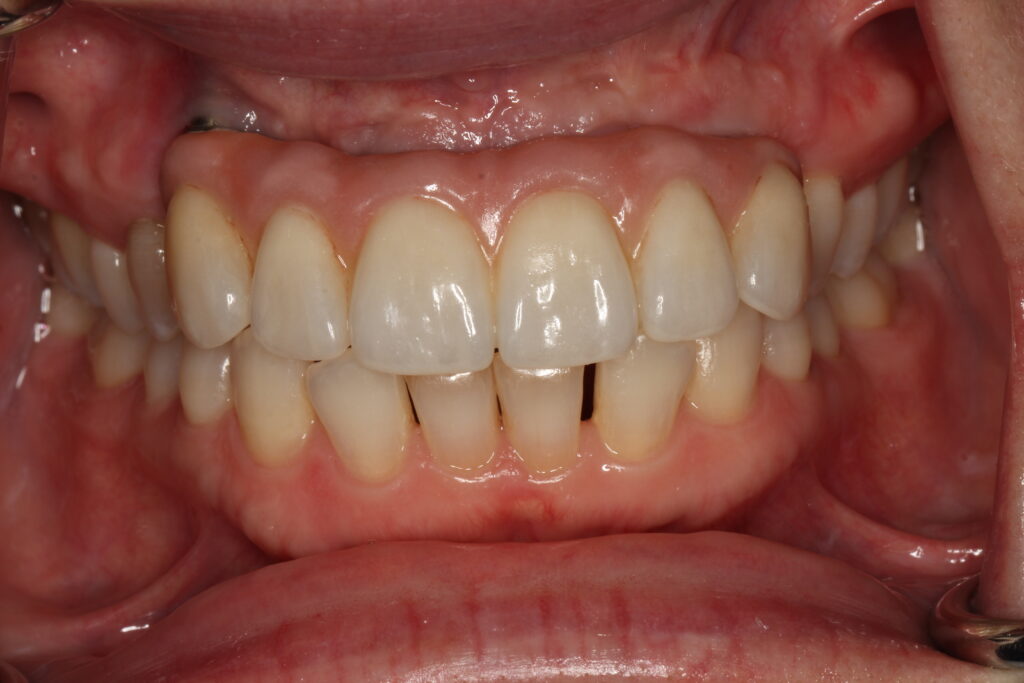

A selection of partial arch fixed implant bridge patients